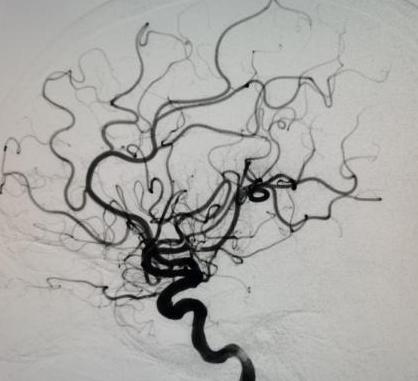

手术由魏华明主治医师操作,10分钟完善术前准备,导管室护士和麻醉师迅速到位,30分钟置鞘成功,40分钟完成脑血管评估,2小时内完成大脑中动脉再通(图二)。术后患者右侧肢体即刻能活动(图三)。术后,神经内一科护理团队密切监护,患者平稳度过7天脑水肿期,现病人言语清楚,右下肢肌力能达到5-级,于3月12日康复出院(图四)。